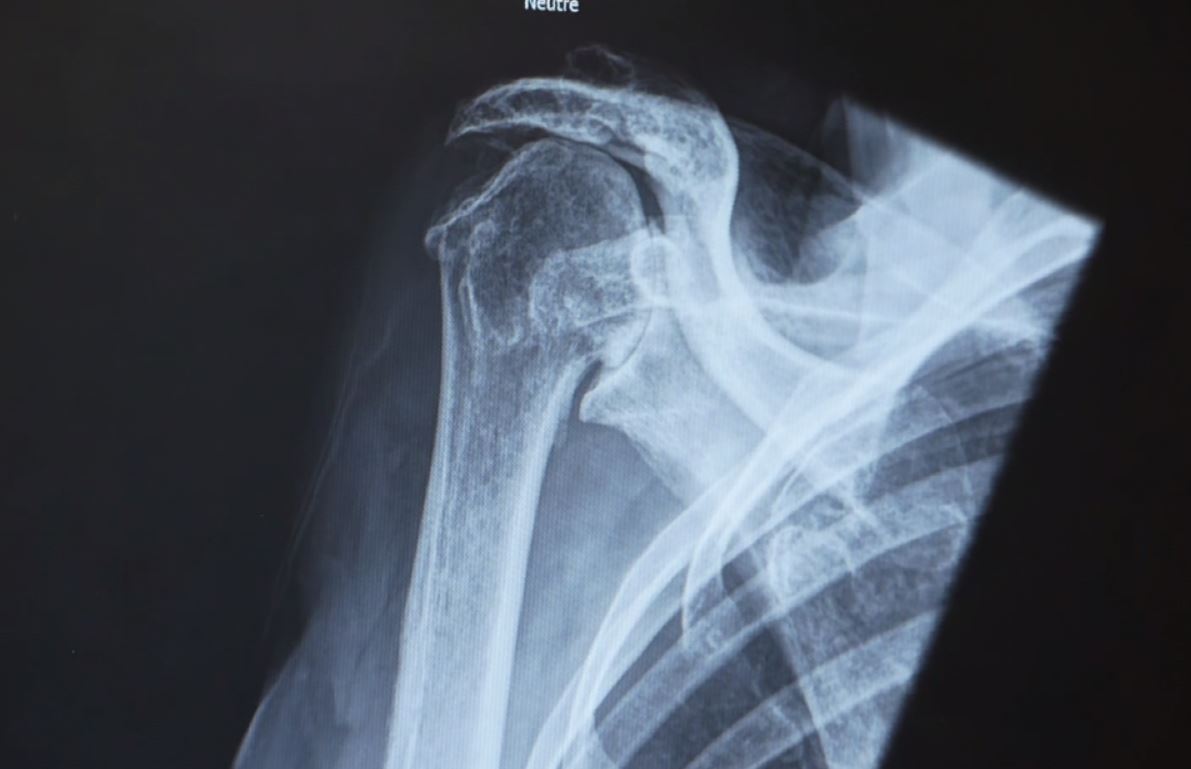

Traumatologie

Vos membres supérieurs, inférieurs et votre colonne vertébrale peuvent être traumatisés dans les suites d’un accident ou dans le cadre de la pratique du sport. Nous assurons votre prise en charge de manière conservatrice ou chirurgicale selon la situation.

Pathologies

• Fracture des os des membres supérieurs et inférieurs

• Fracture de la colonne vertébrale

• Lésions ligamentaires, entorses et luxations articulaires

Traitements

• Traitements chirurgicaux : plaques, clous centro médullaires, vissages, prothèses

• Traitements conservateurs : attelles, plâtres